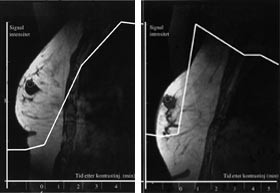

Det pågår en utstrakt forskningsaktivitet for å forbedre det diagnostiske potensialet til MR-undersøkelse av bryst. Ved MR-senteret i Trondheim har vi de siste årene særlig interessert oss for MR-teknikker som avspeiler kapillærgjennomblødningen i tumor, såkalt T2*-vektet førstepassasjebildedanning (fig 2). Bakgrunnen for å anvende denne teknikken er at kreftsvulster har flere og større kapillærer og dermed høyere kapillærperfusjon enn godartede svulster. Foreløpig synes det som om man ved denne teknikken kan påvise brystkreft med høy spesifisitet, men med en noe lavere sensitivitet enn den dynamiske T1-vektede teknikken (20). Siden T2*-vektet perfusjonsbildedanning avhenger av kapillærperfusjonen, kan metoden kanskje gi informasjon om tumorangiogenese (21) og dermed bli et hjelpemiddel både i vurderingen av kreftsvulstens metastaseringspotensial og i evalueringen av behandlingseffekten ved nye former for antitumorterapi som primært retter seg mot svulstens blodforsyning (antiangiogeneseterapi). MR-spektroskopi (MRS), hvor man benytter MR-teknikken til å få metabolsk informasjon fra svulsten, er en annen teknikk som i forskningssammenheng er brukt på brystsvulster. Metabolitten kolin, som inngår i cellemembranenes fosfolipidsyntese, er funnet i betydelige høyere konsentrasjoner i maligne enn i benigne brystsvulster, men det biokjemiske grunnlag for dette og den diagnostiske nytte av MRS i denne sammenheng trenger fortsatt evaluering (22, 23).